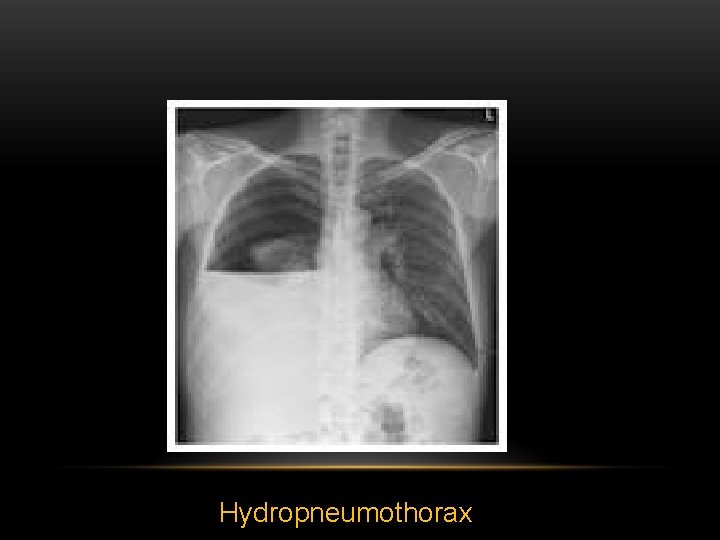

Hydropneumothorax